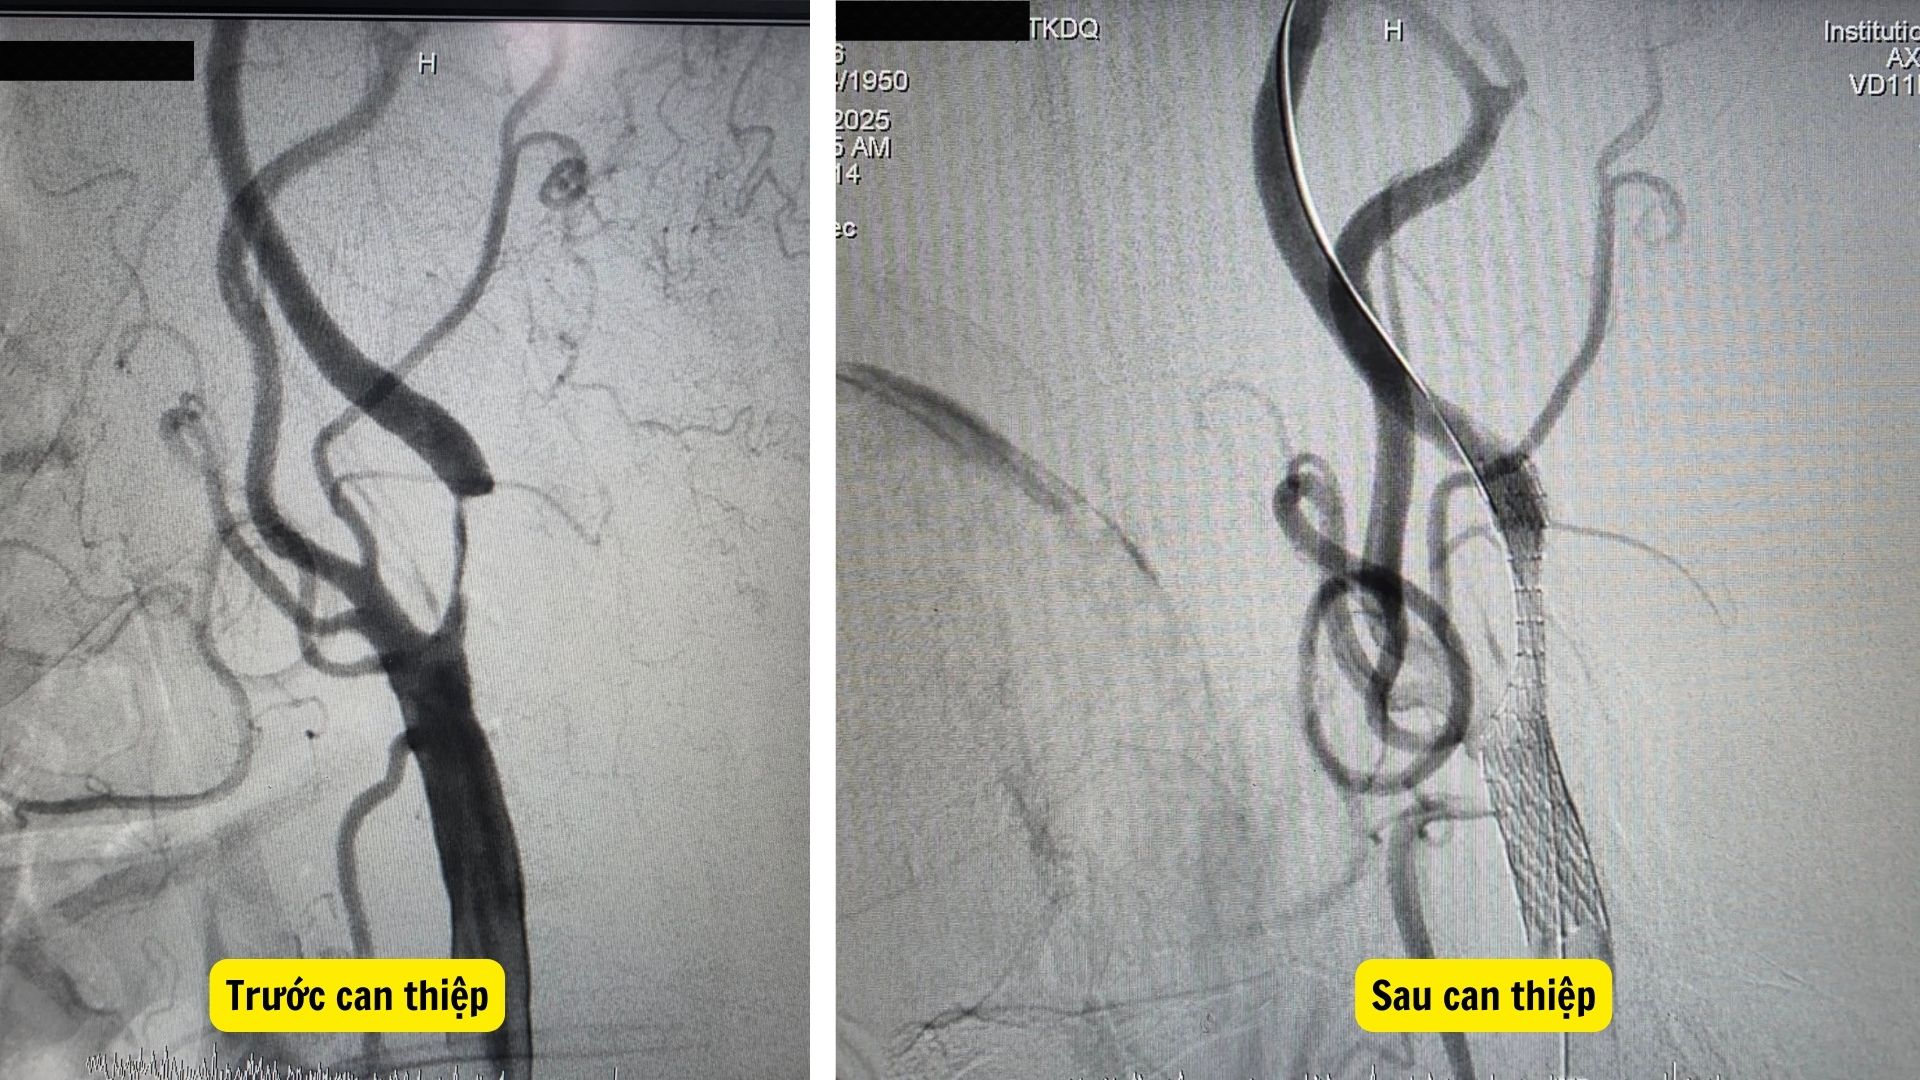

Hình ảnh mạch máu trước và sau khi được tái thông bằng kỹ thuật đặt stent tại Bệnh viện Đa khoa Châu Đốc, cho thấy đoạn động mạch cảnh hẹp nặng đã được mở rộng, dòng chảy phục hồi tốt (Ảnh: BSCC)

Ngày 24/11/2025, ê-kíp can thiệp đã tiến hành đặt stent qua đường ống thông trong lòng mạch máu, tái thông dòng chảy đạt TICI 3 – mức tối ưu trong can thiệp mạch não. Thủ thuật diễn ra trong 45 phút.